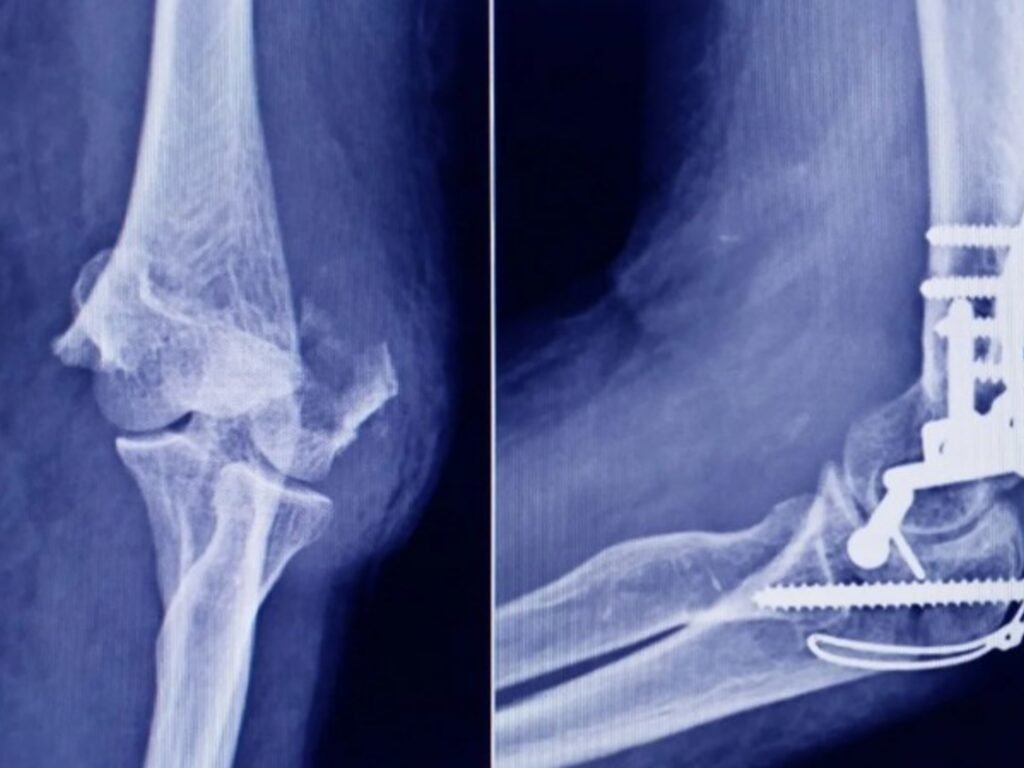

Uncategorized La ANMAT advierte que un tornillo utilizado en cirugías traumatológicas fue falsificado adminhace 3 mesesMenos de 1 min25,0 Vistas Lo encontraron en una ortopedia de San Miguel de Tucumán. El organismo gubernamental marcó las diferencias entre el producto original y el falsificado. Acciones: TE RECOMENDAMOS Uncategorized How to Watch ‘The Voice: Battle of Champions’ Online Without Cable for Free hace 2 meses Uncategorized Eclipses en 2026: cuándo serán, en qué signos y qué cambios energéticos marcarán hace 3 meses Uncategorized Jenni Fagan: Nueve pisos del siglo XX hace 3 meses Uncategorized Independiente: Quinteros está en alerta y no quiere saber nada ante los rumores de ofertas por Lomónaco hace 2 meses Uncategorized sombr, Olivia Rodrigo & Madonna: Which Is Your Favorite New Music Release This Week? Vote! hace 3 días